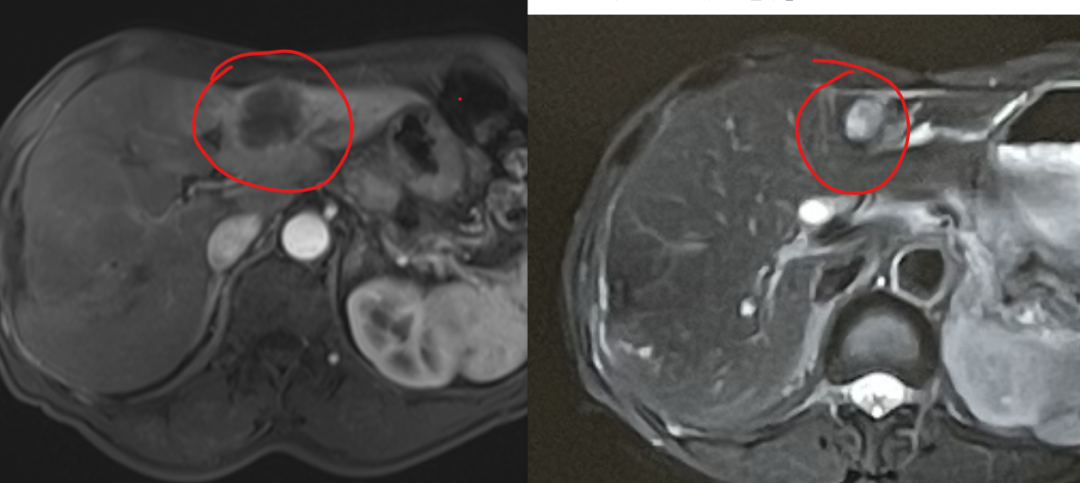

After exhausting conventional options, the family learned about heavy ion therapy’s efficacy in pancreatic cancer through patient communities. They consulted Dr. Chen Weizuo of Wuwei Heavy Ion Center (home to China’s first domestically developed heavy ion therapy system). Following a multidisciplinary expert panel review, Deputy Director Zhang Yanshan explained: "While Mr. Pu has developed resistance to first-line therapies, his high CPS expression suggests carbon ion therapy could enhance local tumor control and reshape the immune microenvironment, potentially re-sensitizing him to immunotherapy." Mr. Pu’s family chose to pursue treatment despite challenges. Over 15 sessions (60 Gy (RBE)/15 fractions for the liver, 58.5 Gy (RBE)/14 fractions for the pancreas), he experienced minimal side effects. Post-treatment, his CA19-9 dropped to 9,450 U/ml. A follow-up in February 2025 revealed further decline to 1,975 U/ml, with significant tumor shrinkage. Encouragingly, he qualified for a clinical trial targeting the KRAS G12D mutation, reigniting his fight.

(Imaging shown: Tumor regression post-carbon ion radiotherapy, left pre-treatment, right 1-month post-treatment.)